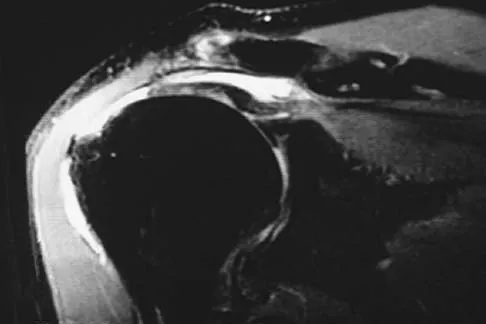

Figure 42 is a transverse MRI scan of the left shoulder. The arrow points to which of the following structures?

A 47-year-old man has acute right shoulder pain after falling off a ladder. The MRI scan shown in Figure 9 reveals